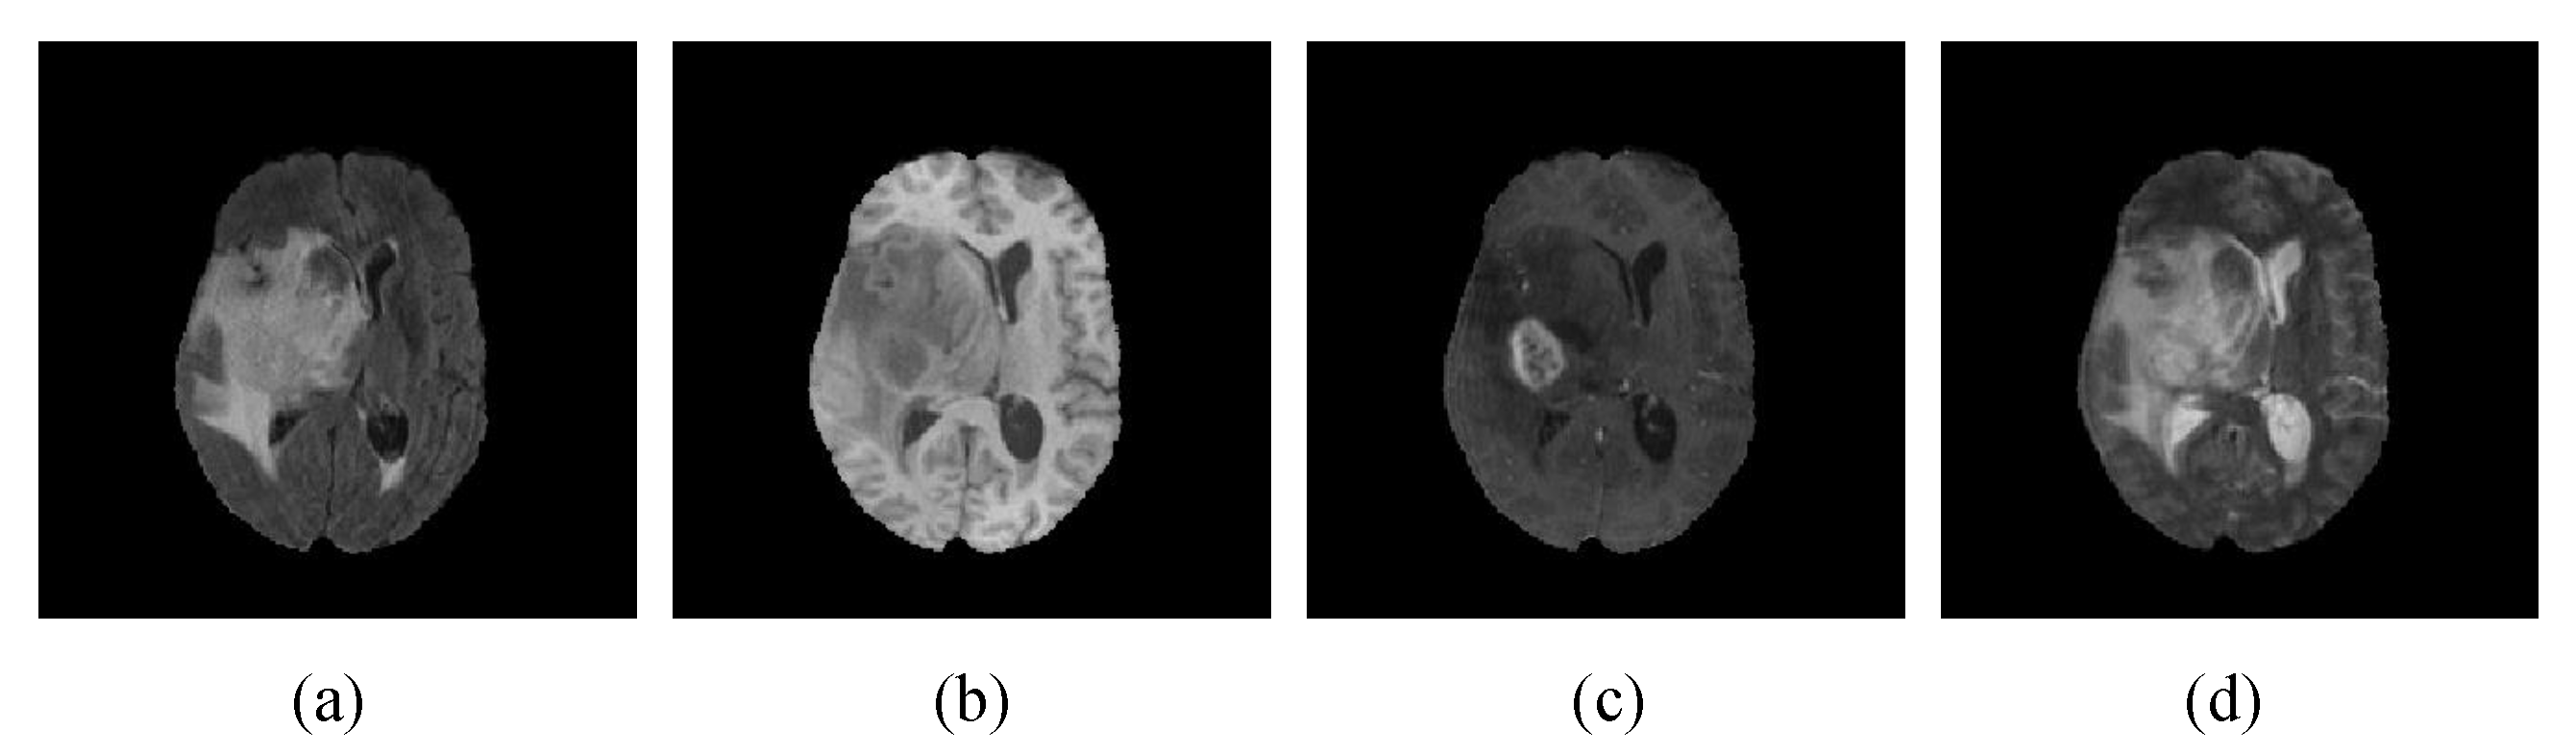

We use the datasets from BraTS2018 and BraTS2020 [33,34] to verify the proposed method. Brain tumor MR images have three tumor tissue classes and one non-tumor category. The three tumor classes were enhanced tumors with a label value of four, peritumor edema with a label value of two, and necrotic and non-enhancing tumors with a label value of one. The BraTS2018 dataset contains 285 cases in the training datasets and 66 cases in the validation datasets. The BraTS2020 dataset contains 369 cases in the training datasets and 125 cases in the validation datasets. Each case includes four sequences of 3D MR data, corresponding to the four modalities of Flair, T1, Tlce, and T2, and each sequence contains 155 slides of size 240 × 240. The four modalities are shown in Figure 5. The three evaluation areas were whole tumor (corresponding to labels 1 + 2 + 4), tumor core (corresponding to labels 1 + 4), and enhanced tumor (corresponding to label 1). The results of brain tumor segmentation can be evaluated on the image processing portal of CBICA, an online evaluation platform. All cases were skull dissected and resampled to isotropic 1 mm2 resolution, while all four sequences of the same case were registered to the same anatomical template for calibration.

Figure 5.

MRI images in different modalities: (a) Flair, (b) T1, (c) T1ce, and (d) T2.